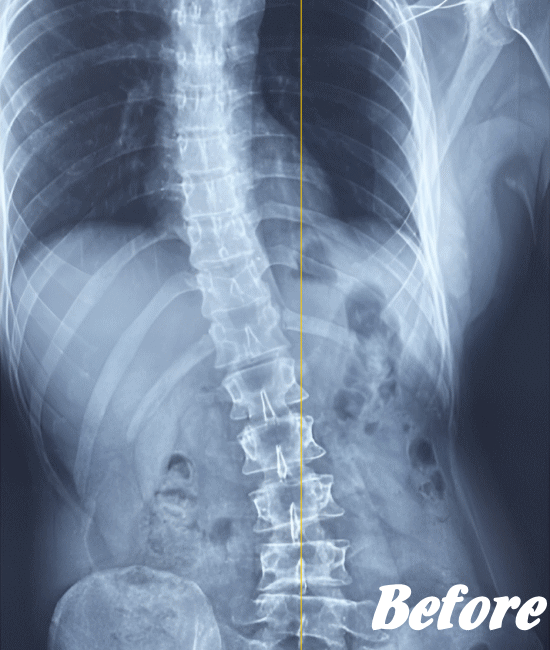

病院では、側弯の程度はレントゲンによる画像検査で弯曲の程度を調べます。

Cobb角(コブ角)とは、背骨の曲がり具合の角度を表す用語ですが、コブ角が10~25度程度なら経過観察。コブ角が25°~40°程度ならコルセットなどの装具を装着する療法、コブ角が40°~50°以上であれば手術…といった目安になります。

先天性や弯曲角度が大きい突発性側弯症は適応外になりますが、普段の姿勢の悪さに起因する機能性側弯症や初~中期の突発性側弯症であれば、施術対象になります。

ただし、弯曲が20°以上になると改善が難しくなってきます。また、脊柱(背骨)が側屈しているだけなら良いのですが、椎骨が回旋してしまっている場合の改善は、肋骨の変形もともなうため改善が難しくなります。